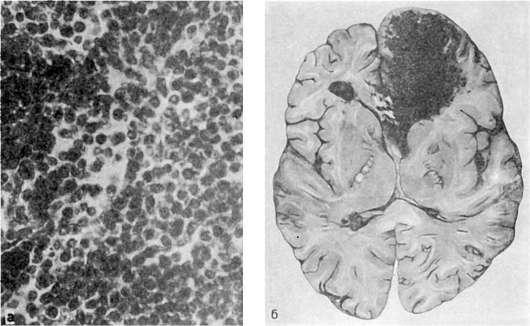

Рис.

а - костный мозг, состоящий из однородных недифференцированных клеток; б - кровоизлияние в лобной доле головного мозга

Острый недифференцированный лейкоз. Он характеризуется инфильтрацией костного мозга (рис. 130), селезенки, лимфатических узлов и лимфоидных образований (миндалины, групповые лимфатические и солитарные фолликулы), слизистых оболочек, стенок сосудов,

миокарда, почек, головного мозга, мозговых оболочек и других органов однородного вида недифференцированными клетками гемопоэза. Гистологическая картина этой лейкозной инфильтрации очень однообразна. Селезенка и печень увеличиваются, но незначительно. Костный мозг плоских и трубчатых костей красный, сочный, иногда с сероватым оттенком. В связи с лейкозной инфильтрацией слизистой оболочки полости рта и ткани миндалин появляются некротический гингивит, тонзиллит - некротическая ангина. Иногда присоединяется вторичная инфекция, и недифференцированный острый лейкоз протекает как септическое заболевание.

Лейкемическая инфильтрация органов и тканей сочетается с явлениями геморрагического синдрома, развитие которого объясняется не только разрушением лейкозными клетками стенок сосудов, но и анемией, нарушением тромбоцитообразования в результате замещения костного мозга недифференцированными клетками гемопоэза. Кровоизлияния различного характера возникают в коже, слизистых оболочках, внутренних органах, довольно часто в головном мозге (см. рис. 130). Больные умирают от кровоизлияния в мозг, желудочнокишечных кровотечений, язвеннонекротических осложнений, сепсиса.